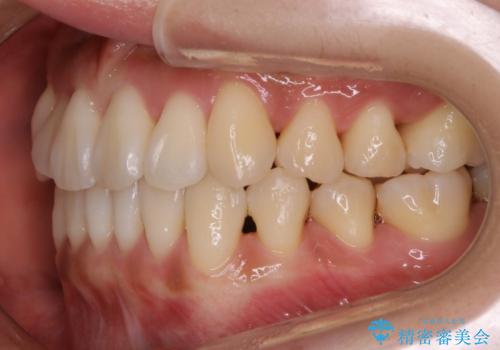

【非抜歯】左右の八重歯・前歯の反対咬合の改善 インビザライン

- 前歯のガタつきを主訴にご来院されました。

診査の結果、骨の厚みに余裕がなく幅の拡大とIPR(歯と歯の間を削り隙間を作る作業)のみでは歯周病に対する不安が残ることが懸念されたため、マイクロインプラントを用いて奥歯から順にすべての歯を後方移動させる方法によってスペースを作ることとなりました。